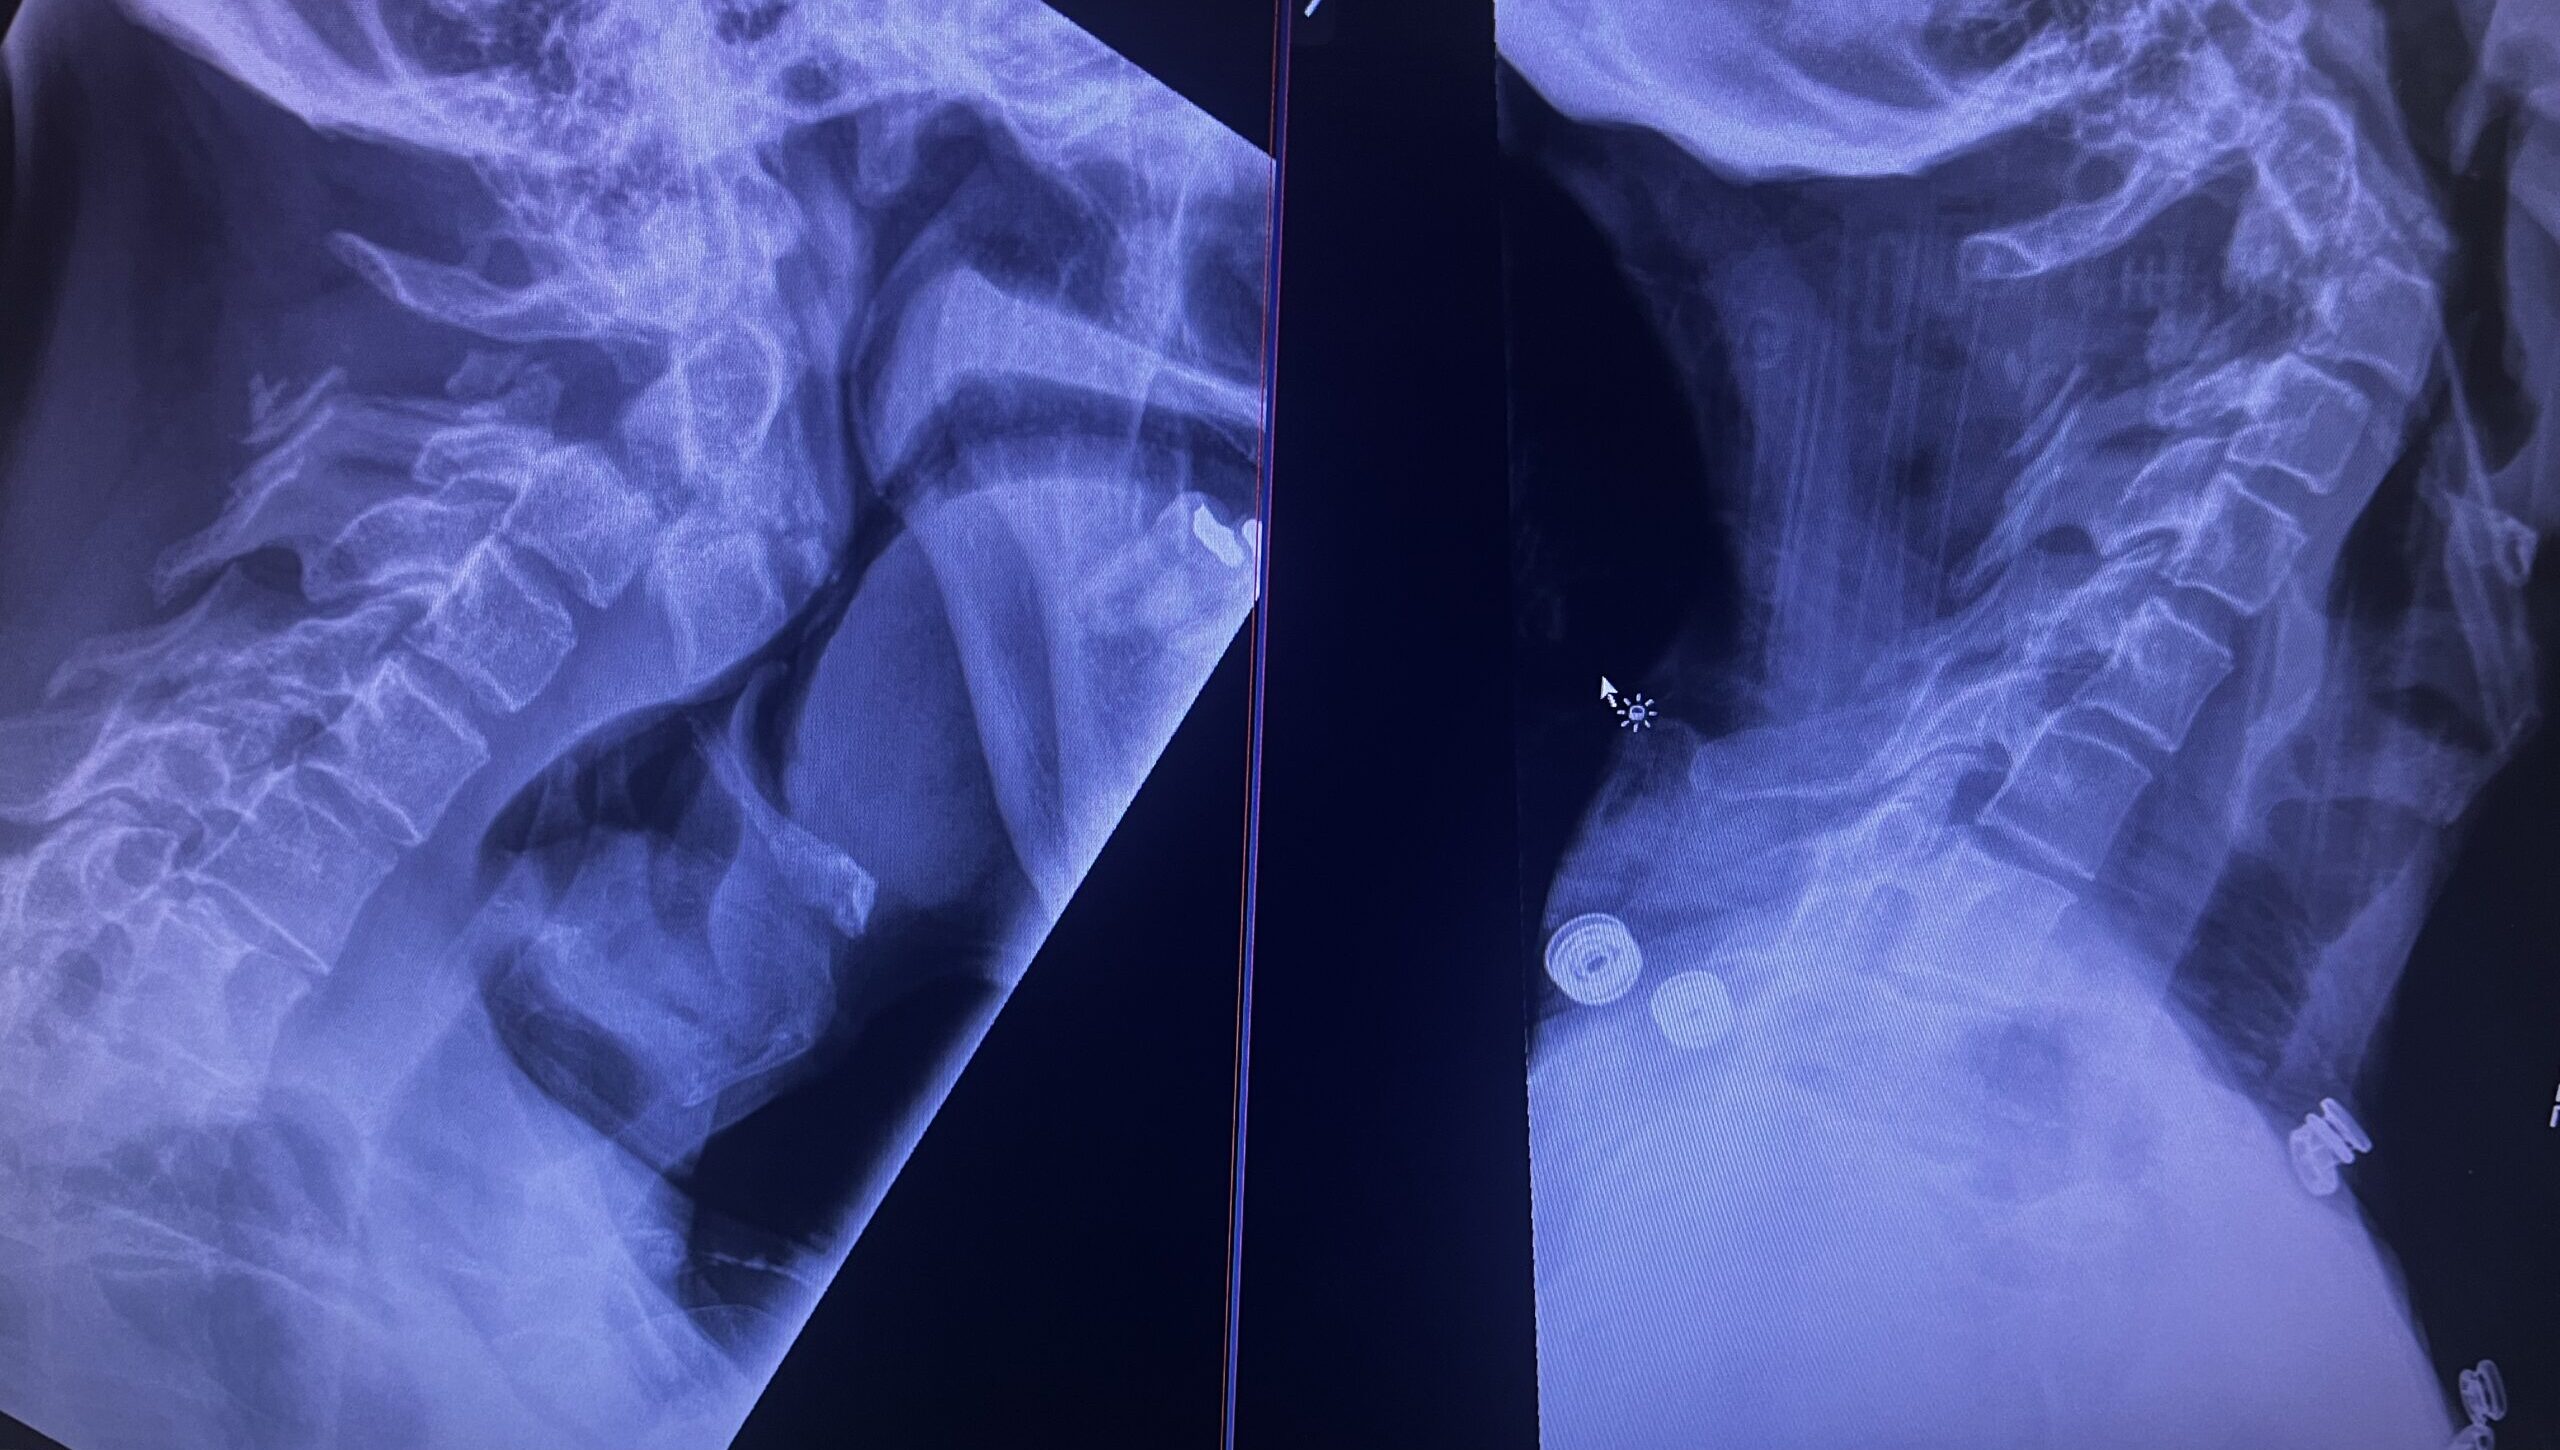

I should have known it was too good to last… a sledding accident at the end of 2021 badly worsened my neck — displacement went from 1.7 to 3.4 mm. In 2022 I had emergency cervical spinal fusion. After the operation I caught pneumonia and my weight fell from 122 pounds to 95 pounds. I am now 5 feet 10 inches tall (I lost an inch from spine compression and an inch from collapsed feet). Swallowing is very difficult. Food gets stuck, my heart rate goes above 100 bpm, and I live on soft or pureed food and shakes. My BMI is approximately 13.6 — under-nutrition.

Recent Imaging Findings

- Chest X-ray Displaced fracture of the right 7th rib, pushed down approximately 1 cm. Narrow thoracic cavity at the top consistent with skeletal dysplasia. Extra soft-tissue calcification around both shoulders. Old T9 vertebral collapse visible. Cervical fusion hardware present. Kyphosis more pronounced.